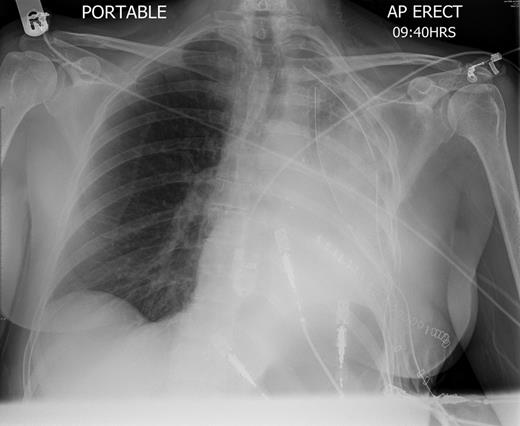

A 57-year-old woman with a left upper lobe mass was referred to our institution for lung resection. Preoperative computed tomography (CT) and positron emission tomography were consistent with lung cancer. Pulmonary function tests revealed a forced expiratory volume in 1 s of 1.64 l (64% predicted), forced vital capacity of 3.1 l (104% predicted) and TLCO of 97% predicted. The patient underwent an uncomplicated left upper lobectomy through open thoracotomy. The fissures were complete, and the inferior pulmonary ligament was mobilized in part. A systematic nodal dissection was performed. She was extubated immediately after surgery and was transferred to the ward as per routine practice. Post-operative chest radiograph revealed satisfactory expansion of the left lower lobe (Fig. 1). On the first operative day, the patient remained haemodynamically stable, without systemic upset, but developed atrial fibrillation with tachycardia. Chest X-ray demonstrated complete opacification of the left hemithorax with normal position of the left hemidiaphragm (Fig. 2). Urgent rigid bronchoscopy revealed narrowed left lower lobe bronchial orifice and the bronchoscope could not pass through. The left upper lobe bronchial stump was intact. Immediate exploratory thoracotomy was performed. At surgery, the left lower lobe had undergone a 180° anti-clockwise torsion at its brochovascular pedicle. The lung parenchyma was very fragile and haemorrhagic, compatible with early venous infarction, hard with a dark reddish surface. Torsion of the lower lobe was corrected and lower lobe was sutured to pericardium, in order to further investigate the anatomy, and determine whether completion pneumonectomy could be avoided. Her AF resolved with restitution of the lobe. A minitracheostomy was inserted prophylactically. However, over the course of the first few post-operative hours, the patient became progressively more hypoxic and tachypnoeic. CT was performed, demonstrating acute obstruction with possible angulation of main pulmonary artery and complete obstruction of left main bronchus (Fig. 3), reported as demonstrating recurrent torsion. The patient returned to theatre for a third time, and at throacotomy, the lobe was found to be in its normal position, but there was now further evidence of infarction, and completion pnuemonectomy was performed. Histological examination confirmed haemorrhagic congestion throughout the left lower lobe parenchyma. Post-operative course was uneventful and patient was discharged home on Day 7.

Chest radiography on the first post-operative day shows left-sided consolidation with normal left hemidiaphragm position.